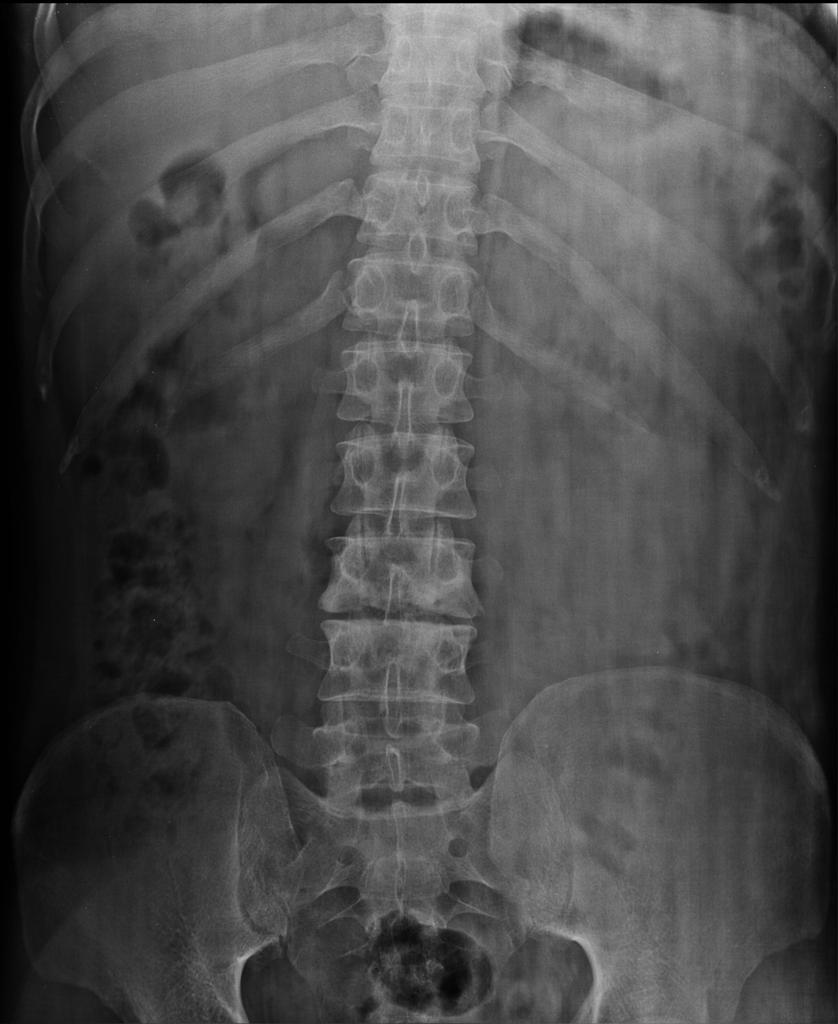

- Воспалительные процессы, развивающиеся в позвоночнике. В частности, остеомиелит, спондилодисцит.

Такое ее расположение и объясняет пути распространения воспалительного процесса. Инфекции позвоночника, которые развиваются в телах позвонков или дисковых промежутках, часто распространяются на соседствующие с ними позвонки. Отсюда гной может истекать вдоль пояснично-повздошной мышцы, вовлекая ее в воспалительный процесс.